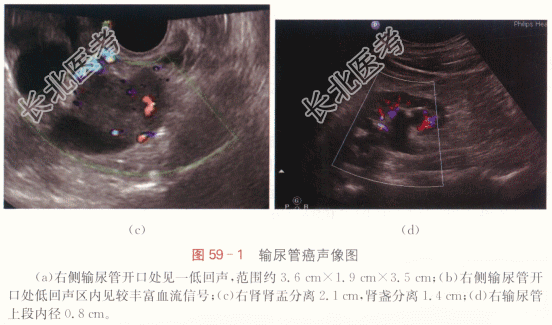

患者,男性,48岁,因“无痛性肉眼血尿半年”就诊。外院超声检查发现右侧输尿管轻度扩张积水,未行特殊诊治。

二、影像资料